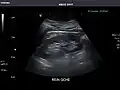

Renal ultrasonography

Ultrasonography of the kidneys is essential in the diagnosis and management of kidney-related diseases. The kidneys are easily examined, and most pathological changes in the kidneys are distinguishable with ultrasound.[7]

Kidneys: Right and left kidneys measure 11.5 cm and 12 cm in length respectively. No hydronephrosis. Small left lower pole kidney cyst.

Right kidney

Left kidney